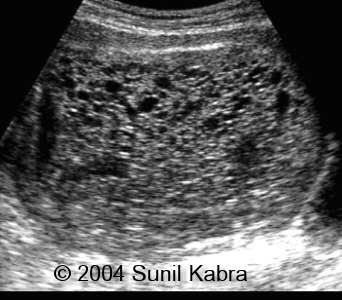

Scan appearance of molar pregnancy on day 27.

Scan Appearance Of Molar Pregnancy On Day 27. | Download Scientific Diagram

Scan appearance of molar pregnancy on day 27. | Download Scientific Diagram www.researchgate.net

molar scan